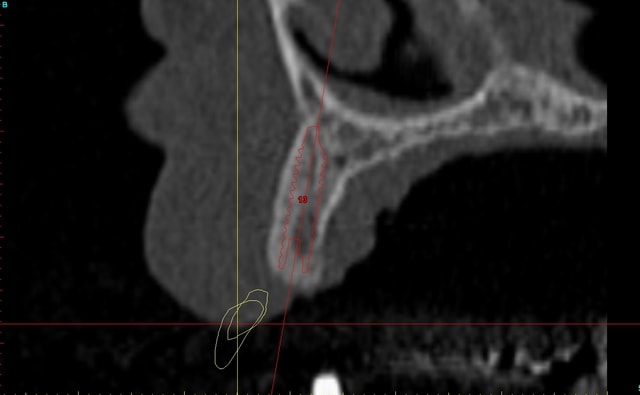

Dar axial lebnbu - Eugenol

Dar axiali qui1is - Eugenol

Dar11 cyo3el - Eugenol

Dar13 alznrp - Eugenol

Dar13i aujibg - Eugenol

Dar14 actm24 - Eugenol

Dar15 zvi82y - Eugenol

Dar23i g6nxds - Eugenol

Dar24 vzfroa - Eugenol

Dar25 lcptyk - Eugenol

Dar 3d xkb3uv - Eugenol

Dar  3di ngfcc4 - Eugenol

Dar  3dl fwmdk6 - Eugenol

Céramik

image 8, il semble y avoir une zone entre le greffon et l'os ?

C'est intégré ?